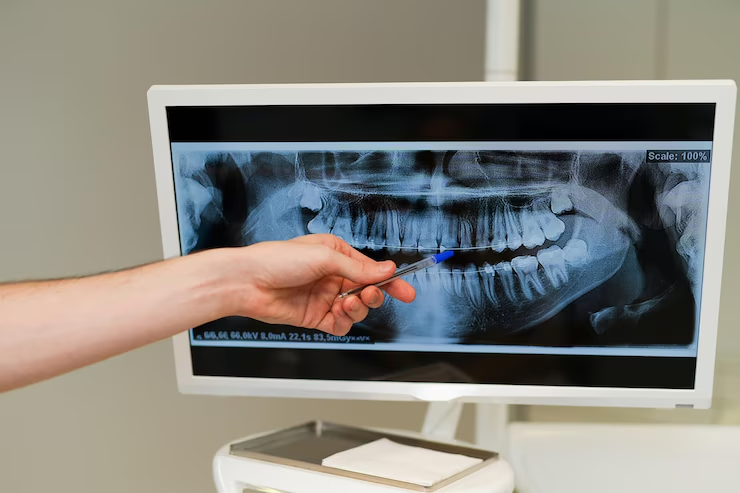

Le panoramique dentaire est une technique d’imagerie médicale qui offre une vue complète de la mâchoire, des dents et des structures environnantes. Bien qu’il soit souvent associé à des diagnostics précis, ses bénéfices vont bien au-delà. Dans cet article, nous explorerons les avantages insoupçonnés que le panoramique dentaire peut apporter à votre santé bucco-dentaire et à votre sourire. Découvrez comment cette technologie peut transformer votre expérience chez le dentiste et contribuer à votre bien-être général.

Le panoramique dentaire permet de détecter des problèmes invisibles à l’œil nu. Grâce à cette technique, les dentistes peuvent identifier des caries cachées, des infections, ou des anomalies structurelles. Cette détection précoce permet une intervention rapide, prévenant ainsi des complications graves et des traitements coûteux. Par exemple, une carie profonde qui pourrait nécessiter une extraction coûteuse peut être traitée à temps grâce à une détection précoce. De plus, le panoramique dentaire est essentiel pour repérer des fractures osseuses subtiles ou des kystes, souvent invisibles sur les radiographies conventionnelles.

Le panoramique dentaire facilite la planification des traitements. Que ce soit pour des implants dentaires, des couronnes, ou des appareils orthodontiques, cette imagerie permet aux dentistes de planifier avec précision chaque étape du traitement. Cela garantit des résultats optimaux et un sourire parfait. Les images panoramiques fournissent des informations détaillées sur la densité osseuse et la structure de la mâchoire, cruciales pour le succès des implants dentaires. En orthodontie, cette vue complète aide à concevoir des plans de traitement qui alignent les dents de manière optimale, en tenant compte des structures sous-jacentes.

Le panoramique dentaire ne se limite pas aux dents. Il offre également une vue détaillée des structures osseuses de la mâchoire. Cette évaluation est cruciale pour détecter des maladies osseuses, telles que l’ostéoporose, et pour planifier des interventions chirurgicales. Une mâchoire saine est essentielle pour la stabilité des dents et le succès des implants dentaires. En détectant les signes de déminéralisation osseuse, les dentistes peuvent recommander des traitements ou des modifications de mode de vie pour renforcer la santé osseuse.

Les images obtenues via le panoramique dentaire facilitent la communication entre le dentiste et le patient. En visualisant clairement les problèmes et les plans de traitement, les patients sont mieux informés et peuvent prendre des décisions éclairées concernant leurs soins dentaires. Cette transparence renforce la confiance entre le patient et le professionnel de santé, et permet au patient de comprendre l’importance des traitements proposés. Un patient bien informé est plus engagé dans son traitement, ce qui améliore les résultats globaux.